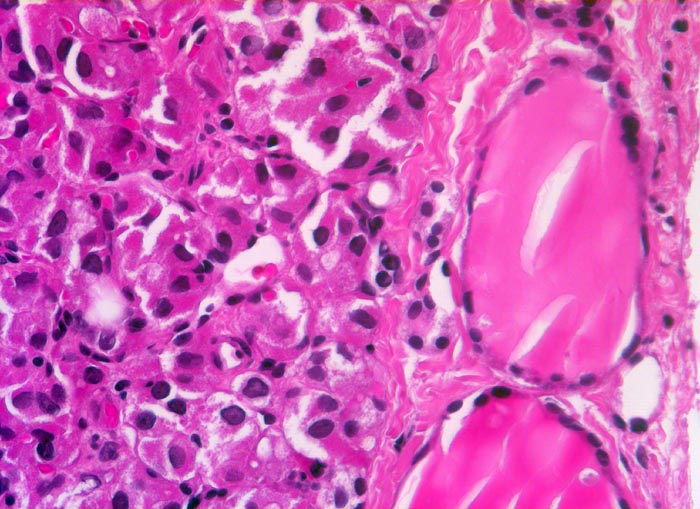

Entscheidend für die Diagnose eines follikulären Schilddrüsenkarzinoms in Abgrenzung zu einem gutartigen follikulären Schilddrüsenadenom ist der Nachweis eines Durchbruchs der Tumorkapsel (> 2753) (> 4951) und/oder ein Einbruch in Venen (> 4953) (> 8265) innerhalb oder jenseits der Tumorkapsel sowie das Fehlen morphologischer Kernmerkmale eines papillären Schilddrüsenkarzinoms. Zytologische Atypien kommen auch bei gutartigen follikulären Adenomen vor und sind deshalb kein Malignitätsmerkmal. Da Kapseldurchbrüche und Gefässeinbrüche nur am Gewebsschnitt diagnostiziert werden können, ist eine präoperative zytologische Diagnose eines follikulären Schilddrüsenkarzinoms anhand der Feinnadelpunktionszytologie nicht möglich.

• Tumorzellen ohne Kernatypien.

• Wenig Kolloid.

• Keine eindeutigen Gefässeinbrüche (keine Tumorthromben oder endothelialisierte Tumorzapfen in Venen der Kapsel oder jenseits der Kapsel). Das sollte der Kliniker dem Pathologen mitteilen: